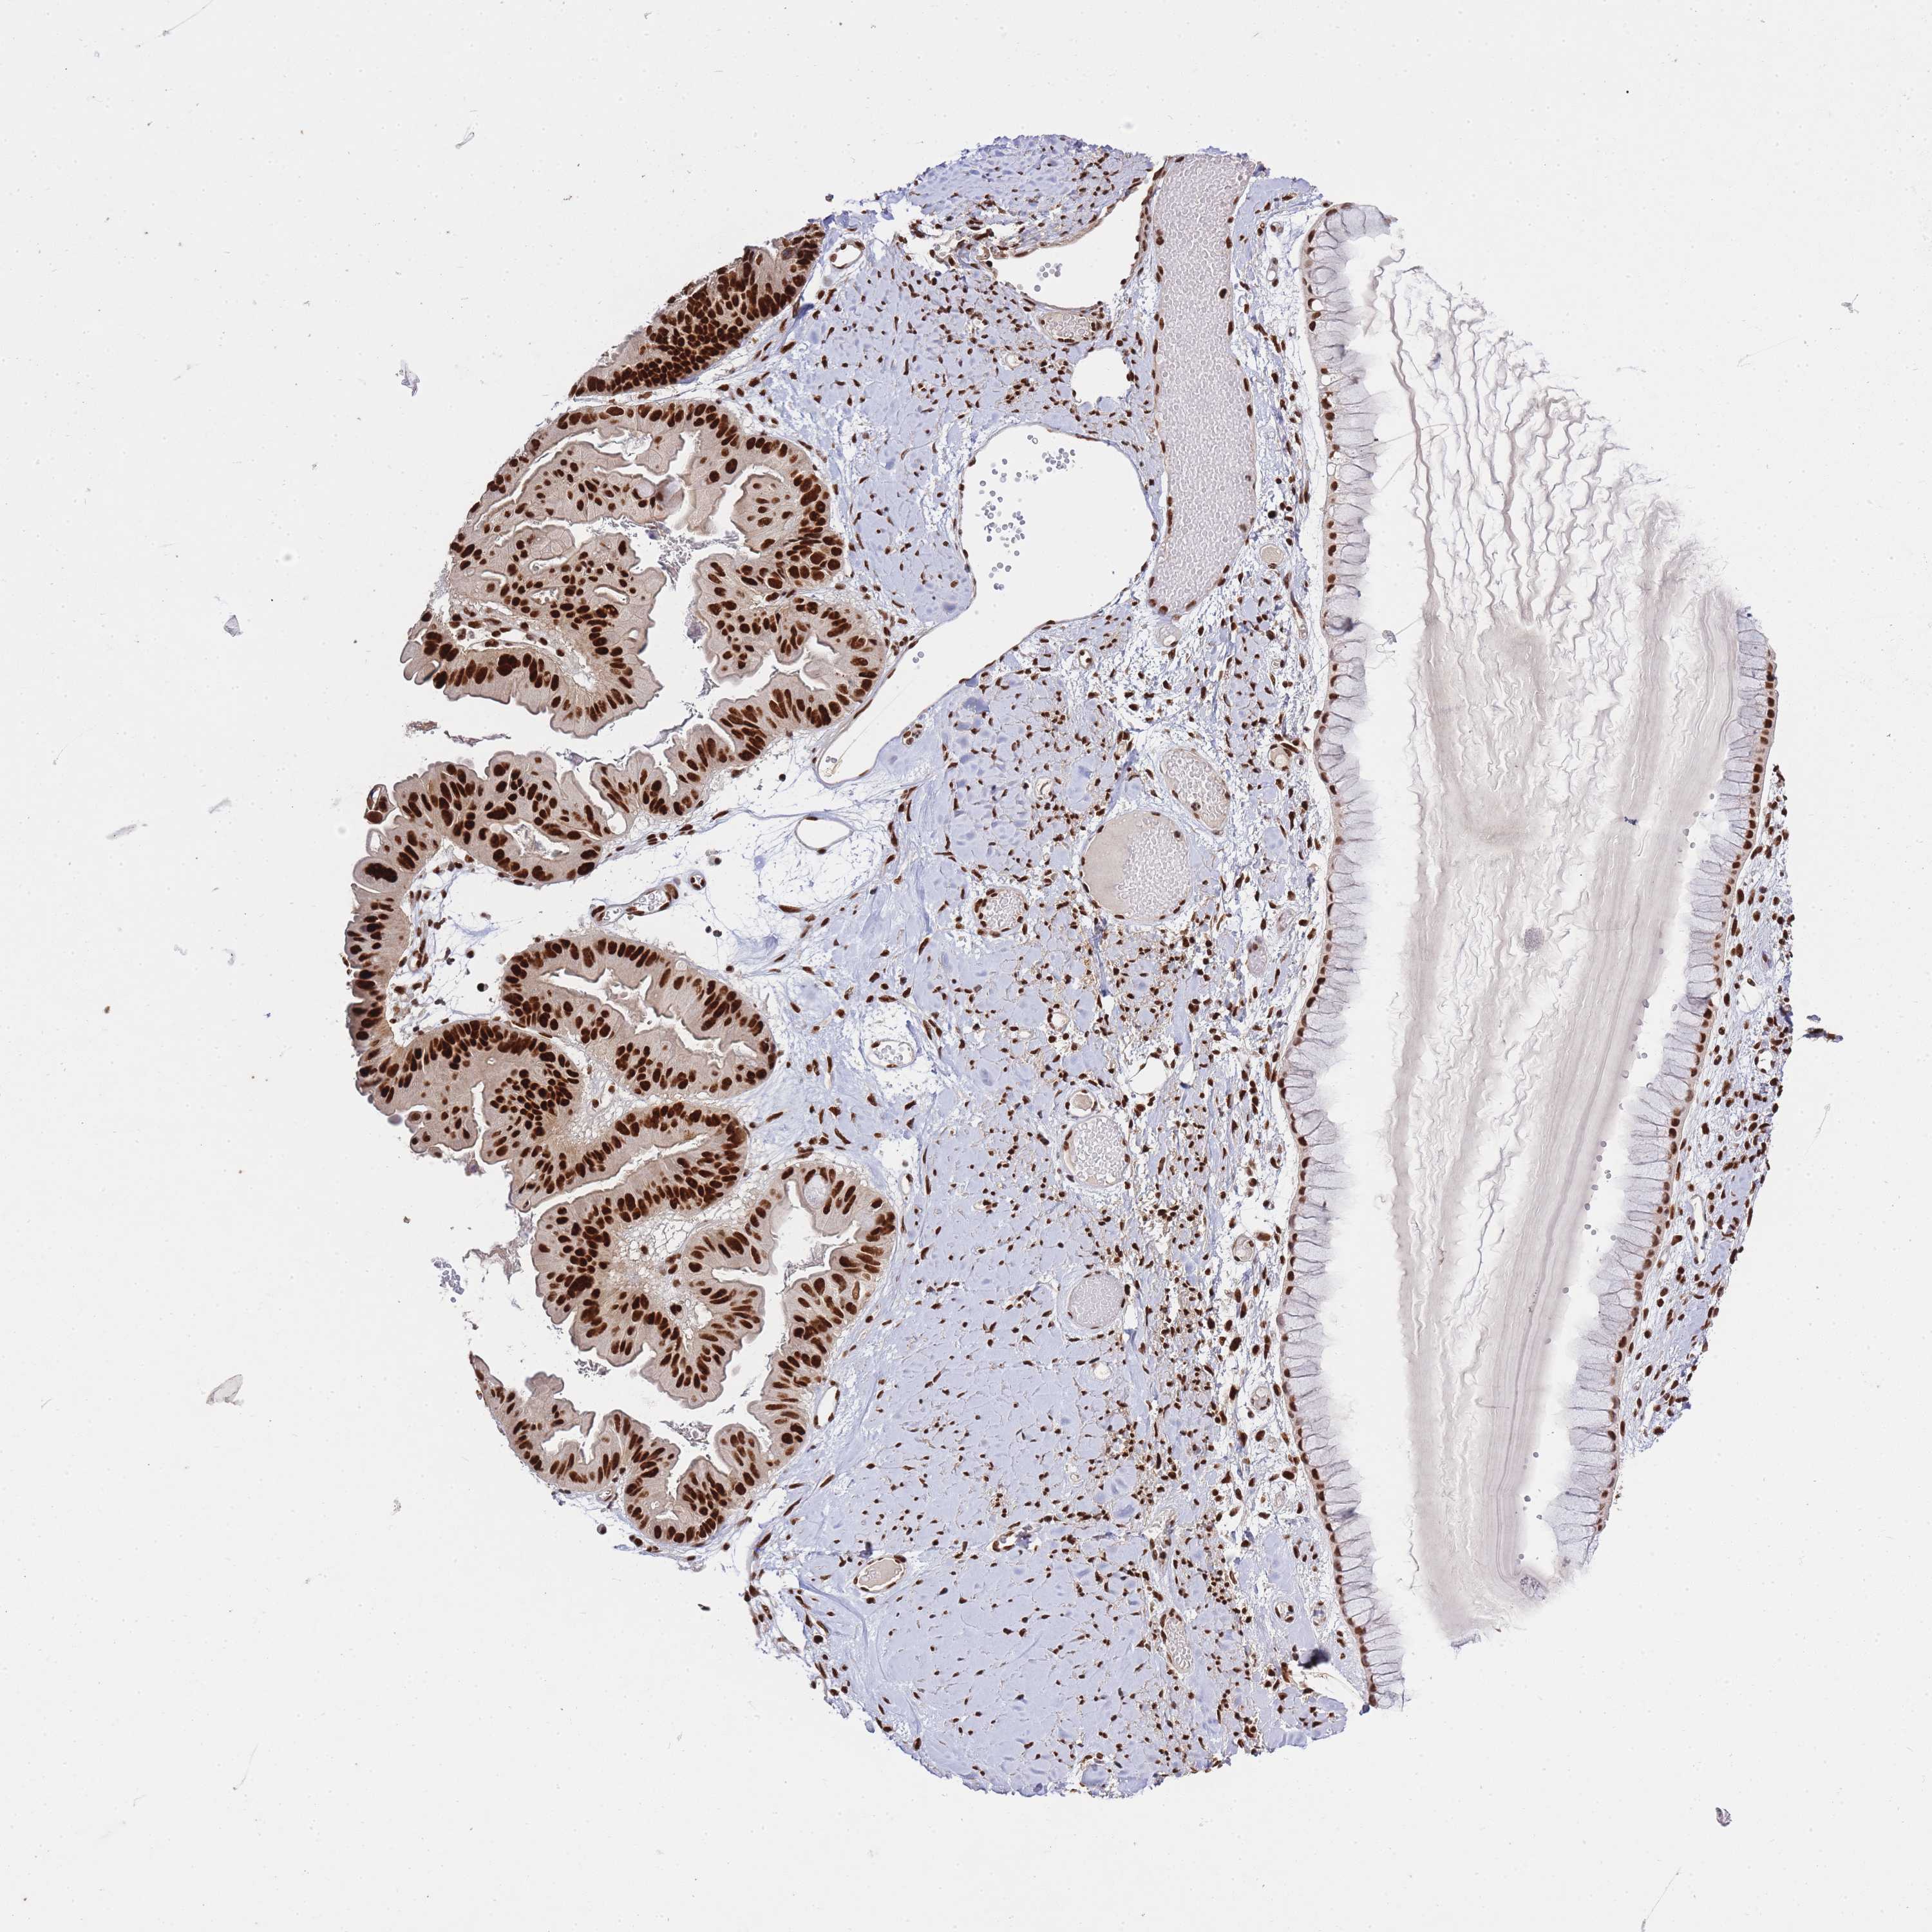

OVARIAN CANCER - Protein expressioni

A mouse-over function shows sample information and annotation data. Click on an image to view it in a full screen mode. Samples can be filtered based on level of antibody staining by selecting one or several of the following categories: high, medium, low and not detected. The assay and annotation is described here.

Note that samples used for immunohistochemistry by the Human Protein Atlas do not correspond to samples in the TCGA dataset.

Antibody stainingi

Antibody staining in the annotated cell types in the current human tissue is reported as not detected, low, medium, or high, based on conventional immunohistochemistry profiling in selected tissues. This score is based on the combination of the staining intensity and fraction of stained cells.

Each image is clickable and will lead to virtual microscopy that enables deeper exploration of all samples and also displays staining intensity scores, fraction scores and subcellular localization as well as patient and tissue information for each sample.

Antibody CAB005167

Cystadenocarcinoma, serous, NOS

Cystadenocarcinoma, mucinous, NOS

Carcinoma, endometroid

Carcinoma, NOS